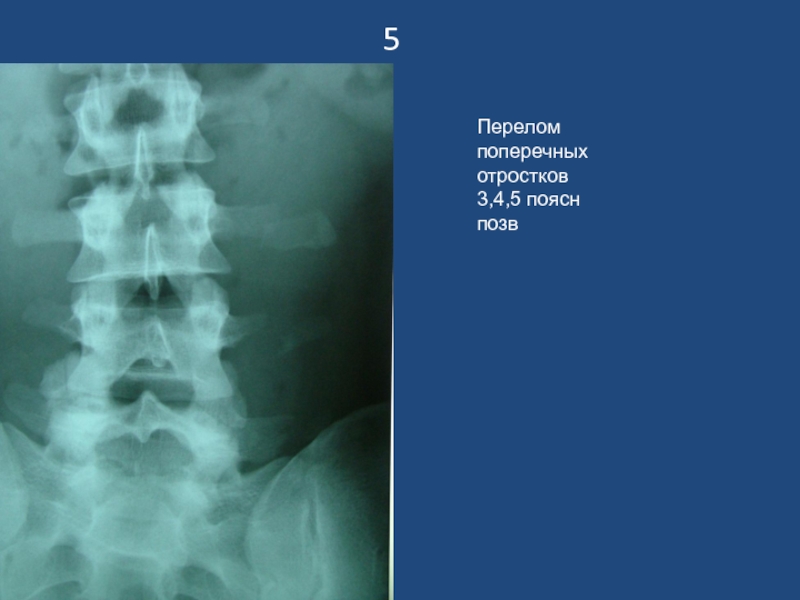

Слайд 65

Перелом поперечных отростков 3,4,5 поясн позв

5Перелом поперечных отростков 3,4,5 поясн позв